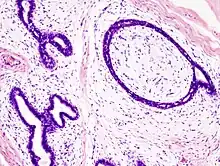

Histopathologic image of breast fibroadenoma. Core needle biopsy. H&E stain.

Microscopic

Fibroadenoma of the breast is a benign tumor composed of a biplastic proliferation of both stromal and epithelial components.[14][15] This biplasia can be arranged in two growth patterns: pericanalicular (stromal proliferation around epithelial structures) and intracanalicular (stromal proliferation compressing the epithelial structures into slit-like spaces).

These tumors characteristically display hypovascular stroma compared to malignant neoplasms.[16][17][11] Furthermore, the epithelial proliferation appears in a single terminal ductal unit and describes duct-like spaces surrounded by a fibroblastic stroma. The basement membrane is intact.[18]